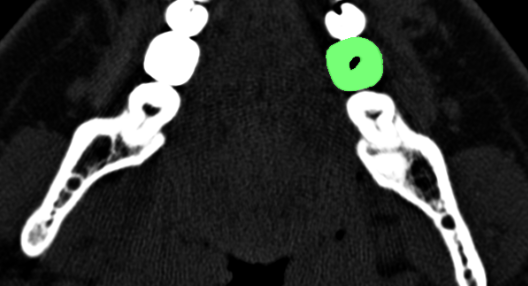

Анимация всех «срезов» зуба и кисты томографом

Ручной процесс сегментирование изображения 36 зуба на КТ в InVesalius очень напоминает процесс создания маски кистью в растровом редакторе.

Автоматическое сегментирование изображения захватывало все костные ткани в изображениях и поэтому не подошло. Если интересно чтобы записал скринкаст процесса создания модели, пишите в комментариях.

Интересно, удавалось ли другим пациентам в такой ситуации доказать реальную степень разрушения зуба. Делает ли какая-либо клиника такую экспертизу? Теоретически, модель зуба может быть объективным аргументом в споре со страховой. По-моему отличная тема для диссертации стоматолога!!!